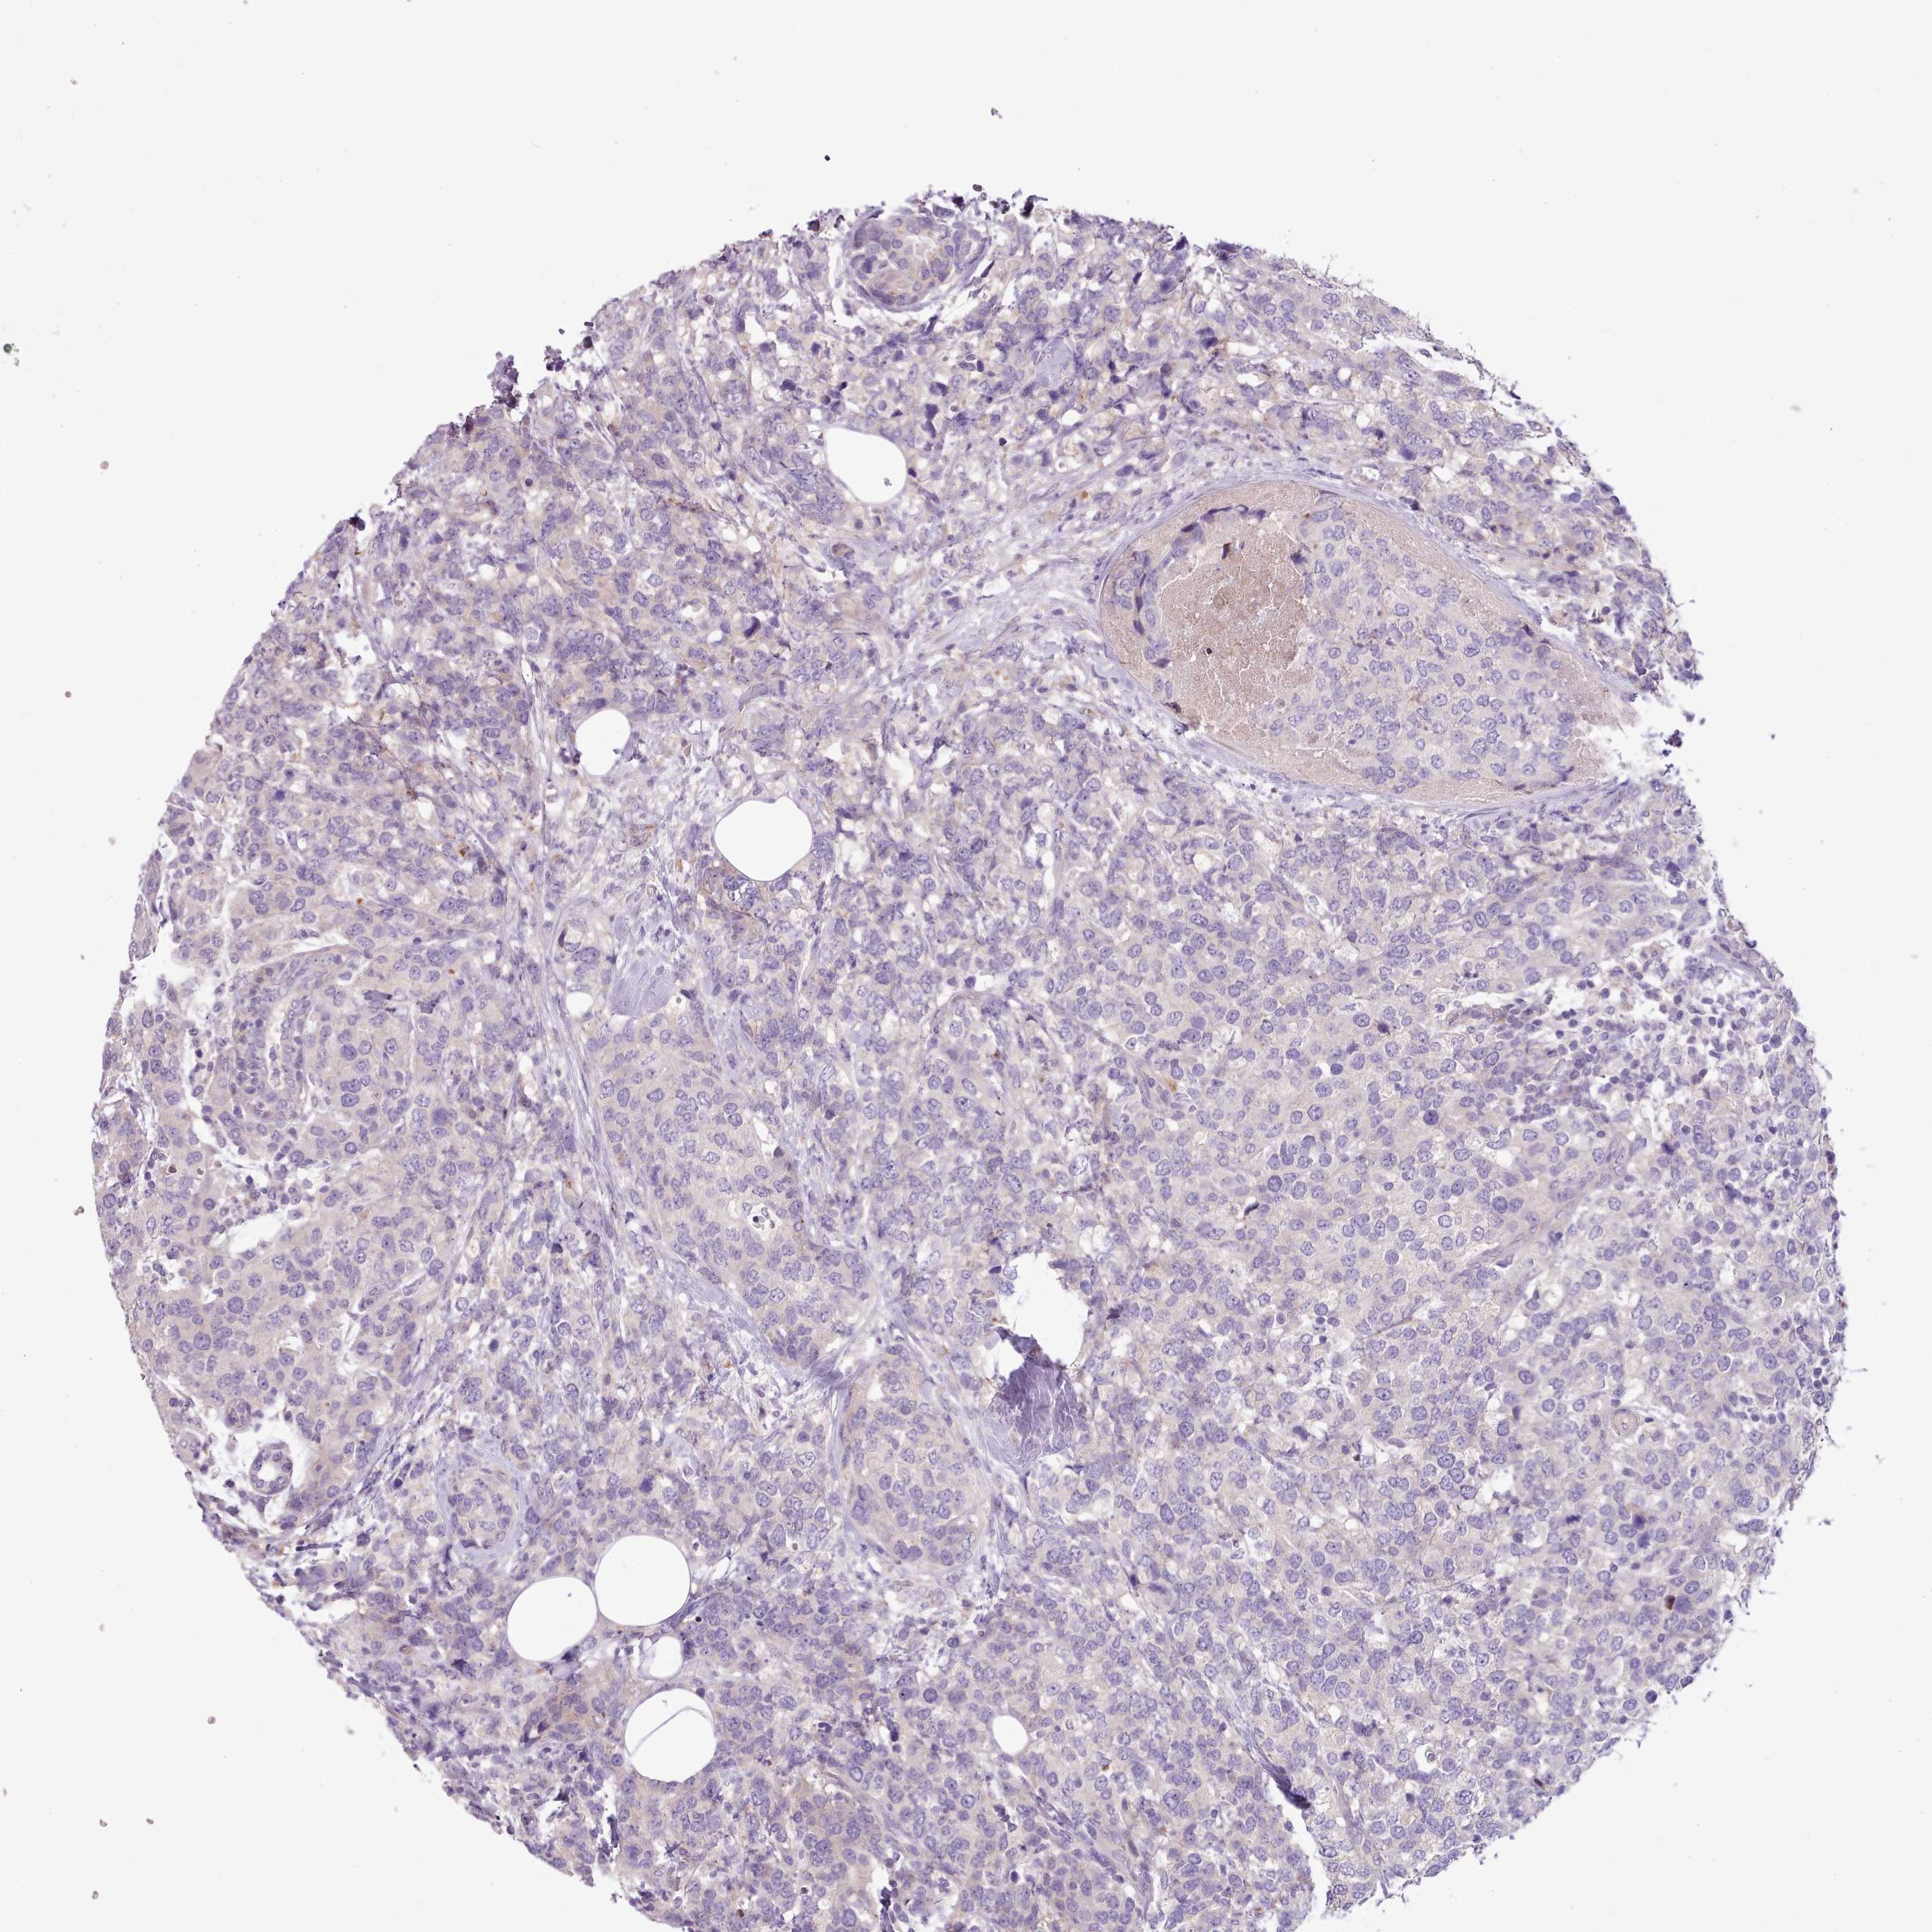

CANCER BREAST CANCER Show tissue menu

BRCA TCGA BRCA VALIDATION PROTEIN EXPRESSION